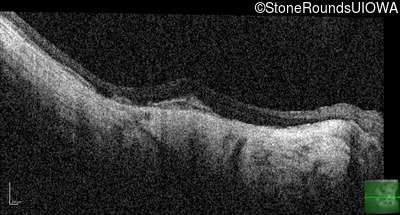

Optical Coherence Tomography - Left - 20/25 +2

Exemplar / OCT Stack

OCT Stack